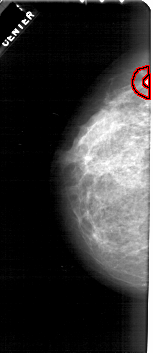

A_1790_1.LEFT_MLO

LEFT_MLO LINES 5446 PIXELS_PER_LINE 2521 BITS_PER_PIXEL 12 RESOLUTION 43.5 OVERLAY

FILE: A_1790_1.LEFT_MLO.OVERLAY

TOTAL_ABNORMALITIES 1

ABNORMALITY 1

LESION_TYPE MASS SHAPE IRREGULAR MARGINS SPICULATED

ASSESSMENT 4

SUBTLETY 1

PATHOLOGY MALIGNANT

TOTAL_OUTLINES 2

BOUNDARY

CORE